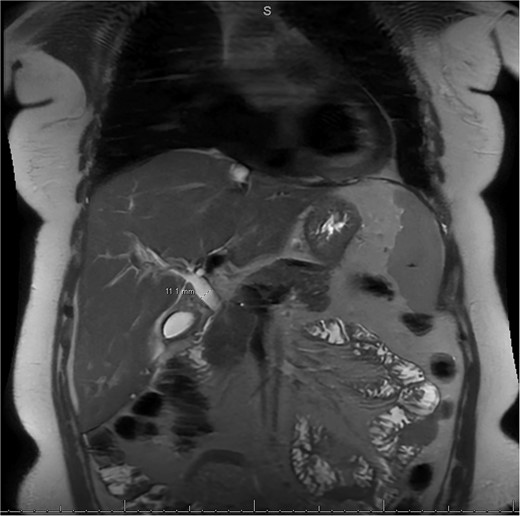

MRI/MRCP from second hospitalization demonstrating recurrent cholelithiasis.

A 49-year-old female with a history of ADPKD and multiple liver cysts, 13-months status post subtotal cholecystectomy, endoscopic retrograde cholangiopancreatography with biliary sphincterotomy and balloon stone extraction, presented to the emergency department with fever and a 4-day history of discomfort in the right upper quadrant. At the time of the initial cholecystectomy, total cholecystectomy could not be performed due to extensive adhesions, and subtotal cholecystectomy with complete evacuation of the stones was done instead. Magnetic resonance cholangiopancreatography (MRCP) done at that time showed a dilated common bile duct (CBD) to 1.5 cm, intra and extrahepatic biliary dilatation, multiple liver cysts measuring up to 2 cm, and multiple stones in the CBD, including at the level of the ampulla (Fig. 1). Computerized tomography scan at the time of the second admission showed acute cholecystitis and she had mildly elevated transaminases, but there was no evidence of cholestasis or pancreatitis. MRCP showed minor proximal intrahepatic biliary dilation and cholelithiasis but no duct calculi (Figs 2–4). A laparoscopic cholecystectomy was attempted with extensive adhesiolysis between the gallbladder and surrounding omentum and mesocolon, but the cystic duct could not be isolated, and ultimately the cased was converted to open. While removing the gallbladder in a top-down fashion, a small bile leak was identified right at the closed end of the gallbladder remnant, where the bile duct was adhered to the gallbladder wall. Intraoperative cholangiogram was obtained through a small perforation in a right posterior bile duct at the site of attachment, which showed right posterior, right anterior and left hepatic ducts of equal size converged at a trifurcation (Fig. 5). The duct was repaired over a T-tube and observed throughout the rest of the case and no bile leak was identified. The gallbladder was opened along its lateral edge, revealing a hugely dilated cystic duct with ~10 to 12 marble-sized stones packed within the gallbladder remnant and cystic duct down to the juncture with the common bile duct. All the stones were removed and the safe portion of the gallbladder remnant was resected leaving the side attached to the bile duct in situ due to the Mirizzi anatomical variant. The cystic duct was oversewn along with the remnant of the gallbladder wall. Pathology showed acute-on-chronic cholecystitis with cholelithiasis. Repeat MRCP showed no retained stones in the biliary tree. The recovery course was unremarkable.